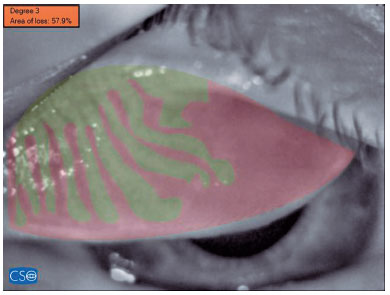

3. Meibography was then performed in the right upper and lower eyelid of the patient, with at least five images acquired for each eyelid. The three images with the best contrast and image quality were analyzed and marked manually by ophthalmologist (Y.A.). They were also processed using specialized software. The patient’s meibomian gland dropout rate was categorized using a five-point grading system as follows: grade 0, no dropout; grade 1, <25% dropout; grade 2, 26-50% dropout; grade 3, 51-75% dropout; grade 4, >75% dropout(10). The average grade and dropout rate determined for the above-mentioned three images were recorded and later used for statistical analyses.

The device renders the meibomian glands using an infrared (IR) light source. Then, four separate points are marked on the image to delineate the eyelid under examination. The area within these four points is depicted as a roughly trapezoid shape. The inner part of the trapezoid is manually screened for MG by the user of the device and automatically highlighted in green. The remaining part of the trapezoid, i.e., that which does not contain meibomian glands, is automatically highlighted in red. The proportion of the total trapezoid area that is colored red provides the MG dropout rate for the eyelid scanned, both as a percentage and as a grade on the five-point grading system described above(10) (Figure 2).

Based on the five-point grading system(10), the superior meibography (SM), which is that of the upper eyelid, showed grade 1, grade 2, and grade 3 dropouts in 27 (37%), 34 (46.6%), and 12 (16.4%) patients, respectively. In Group 2, these grades occurred in 62 (92.5%), 5 (7.5%), and 0 (0.0%) of participants, respectively. The difference between groups was statistically significant (p=0.000). The inferior meibography (IM), which is that of the lower eyelid, showed grade 1, grade 2, and grade 3 dropouts in seven (9.6%), 37 (50.7%), and 29 (39.7%) of the patients in Group 1, respectively. In Group 2, these grades occurred in 48 (71.6%), 18 (26.9%), and one (1.5%) of the participants, respectively. Again, there was a significant difference between the two groups (p=0.000) (Table 1).

The mean MG dropout percentages found by superior meibography (SM) were 33.0 ± 15.5% in Group 1 and 15.7 ± 6.9% in Group 2 (p=0.000). The average percentages found by inferior meibography were 45.4 ± 14.5% in Group 1 and 21 ± 9.7% in Group 2 (p=0.000). The difference between groups was statistically significant for both eyelids (Table 1, Figures 2 and 3).